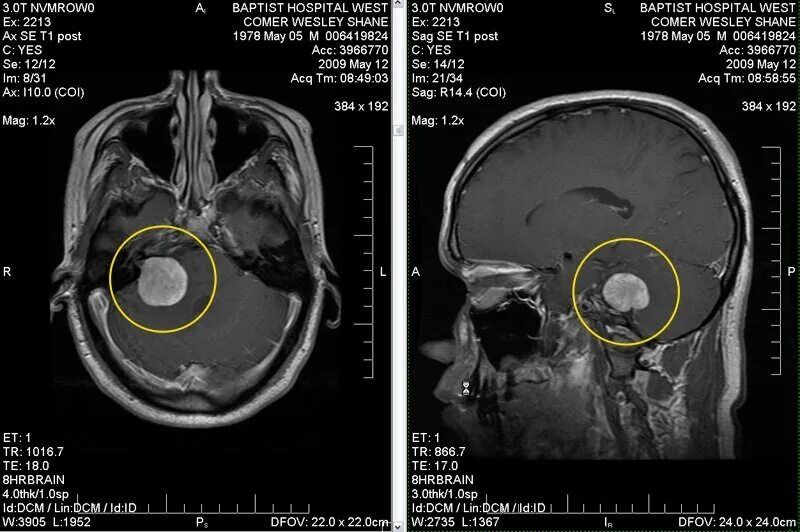

Какие опухоли в голове